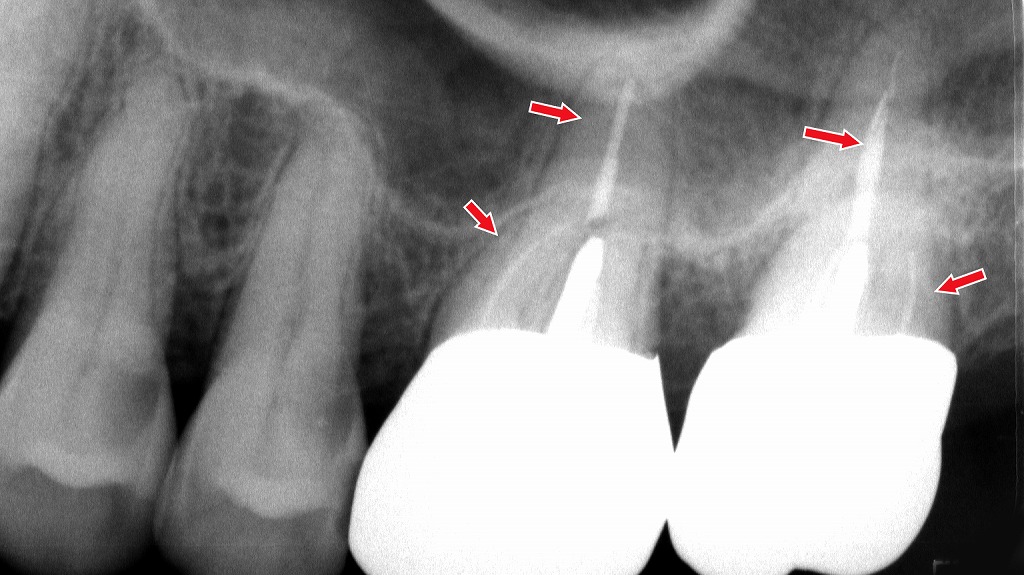

🪥 歯石取り・歯周治療

歯周病が原因の場合は、歯石除去や歯ぐきの治療が中心となります。

歯が「浮く感じ」は、歯石の沈着と歯周病による炎症が主な原因です。本症例では、左半分(画像では右側)に歯石除去・歯周治療を実施したとろろです。一方、未処置側には歯石が多く残存しています。歯石取りと適切な歯周治療を行うことで、歯の違和感や浮く症状は改善が期待できます。

🔬 根管治療(神経の治療)

神経が炎症を起こしている場合は、根管治療で炎症を取り除きます。

レントゲンでは、矢印部の根管にしっかりと薬剤が充填されており、根尖部に炎症や膿を示す黒い影(根尖病変)は認められません。

根管治療が適切に完了している状態で、歯の内部感染は取り除かれています。